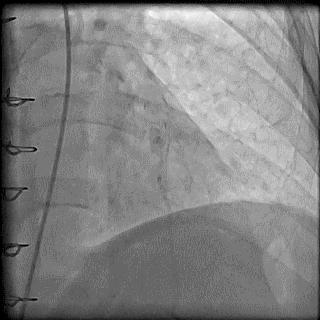

(4)LIMA桥血管造影

首选导管:JR4.0导管

其他导管:如果开口明显成角应选用专用的内乳动脉造影导管

➢ CASE 6

经股动脉途径TIG,非选择造影如果能清晰显影,可不做超选造影

➢ CASE 7

经左侧桡动脉途径JR4.0,非选择造影如果能清晰显影,可不做超选造影